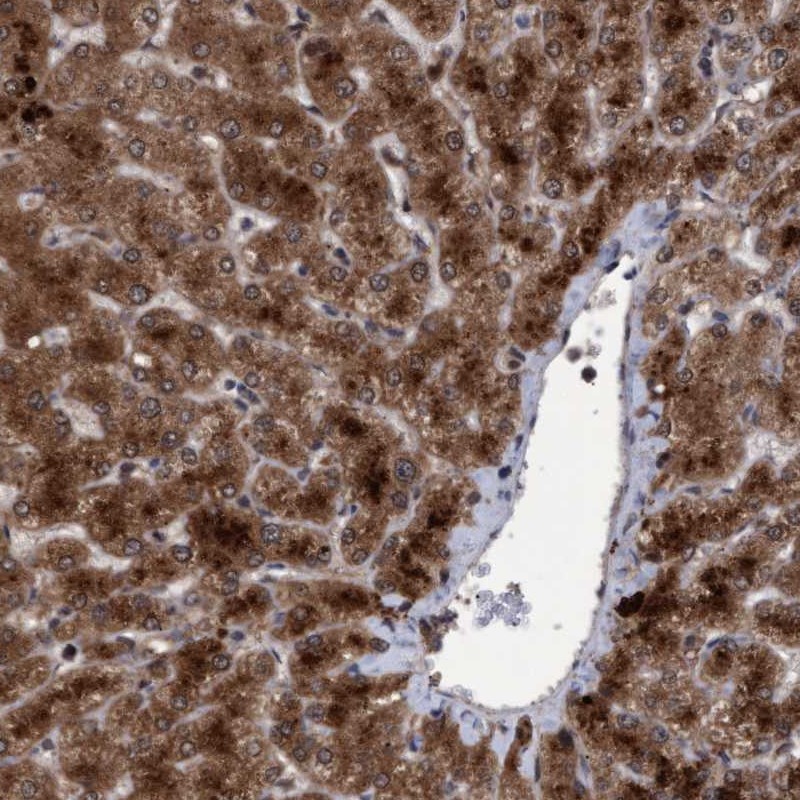

Immunohistochemical staining of human liver shows strong cytoplasmic positivity in hepatocytes.